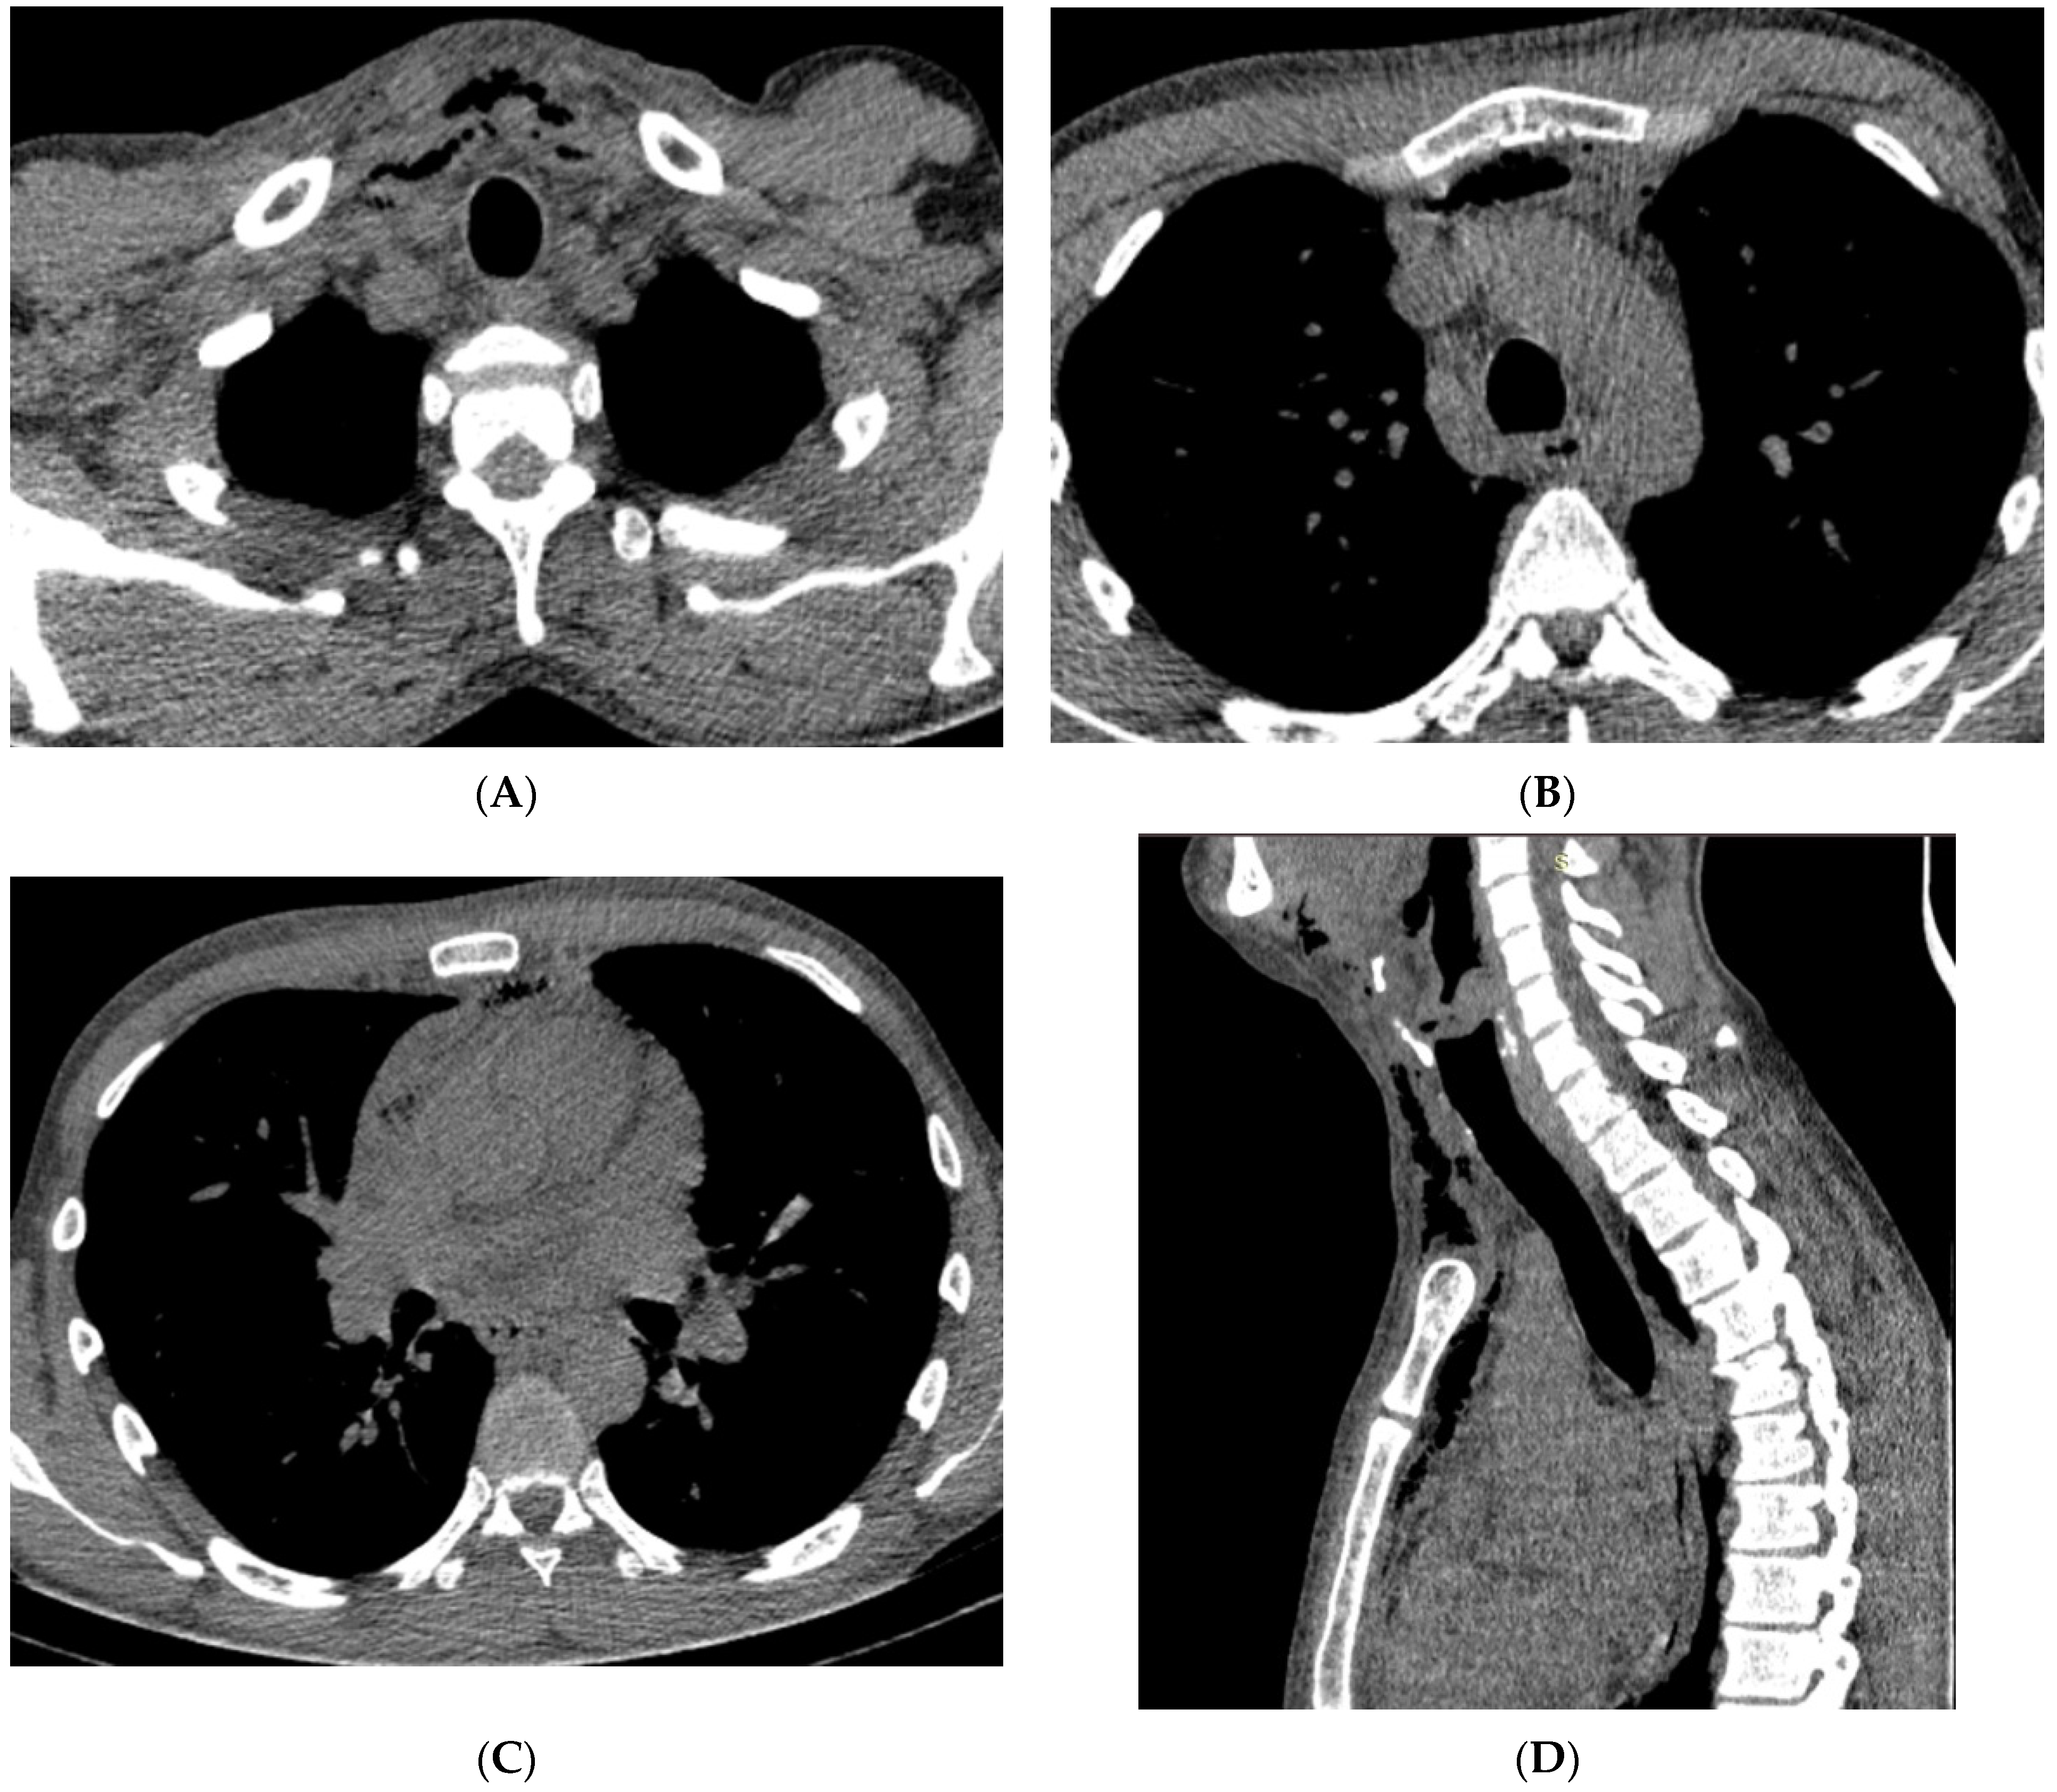

| Neck CT | Pus collection - in the left submandibular area - around the hyoid bone - around the left piriform recessus - around the thyroid cartilage - around the sternocleidomastoid muscle | Presence of a gas collection with delamination of the soft tissues of the neck in the area of the parapharyngeal space on the left Gas collections in - both palatine tonsils - anterior cervical space - left carotid space up to the level of the aortic arch - bilateral submandibular and sublingual space | Multiple air collections that stratify the tissues of the neck on the right side | Multiple air collections that stratify the superficial and deep tissues of the neck and enter the mediastinum |

| Chest CT | pus collection: ventral from the thyroid gland measuring 68/14 mm, with a density of 34–40 HU reaching the carina | Purulent collection starting from the neck and reaching the anterior mediastinum above the carina, presence of gas collections | Multiple air collections involving all departments of the anterior mediastinum above the carina | Massive pneumomediastinum, presence of fluid-purulent collections in the anterior and posterior lower mediastinum below the carina |

| Surgery | remediating the source of infection and suprasternal mediastinal drainage | Remediating the source of infection and suprasternal mediastinal drainage | Remediating the source of infection and suprasternal mediastinal drainage | Remediating the source of infection and thoracotomy |